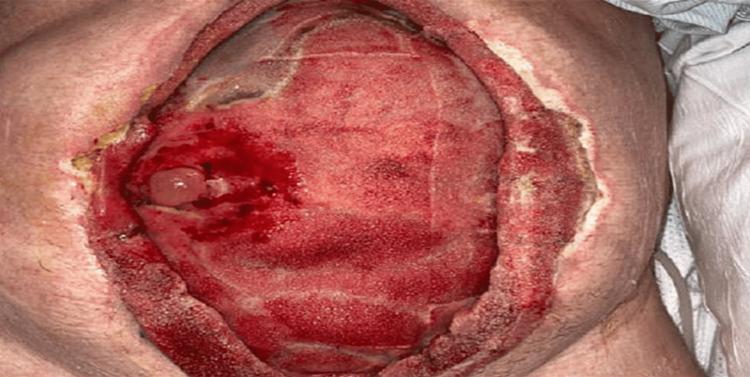

Enteroatmospheric fistula (EAF) is a relatively rare complication of patients undergoing open abdomen (OA) for damage control surgery. Mortality rates are high due to the increased risk of peritonitis, intraabdominal abscess, sepsis, and new perforations. There are a wide range of EAF management therapies in the literature, however, there are limited options on cases involving fistula-vaccum assisted closure (VAC) therapy. This case describes the treatment course of a 57-year-old, male admitted for blunt abdominal trauma secondary to a motor vehicle accident. Upon admission the patient underwent damage control surgery. The surgeons elected to have the patient's abdomen open, applying a mesh to promote healing. After several weeks of hospitalization an EAF was discovered in the abdominal wound subsequently managed by utilizing a fistula-VAC technique. Based on the successful outcome of this patient, fistula-VAC was shown as an effective way to promote wound healing while reducing the chances of complications.

肠-腹壁瘘(EAF)是接受开放性腹腔(OA)损伤控制手术患者相对罕见的并发症。由于腹膜炎、腹腔内脓肿、败血症和新穿孔风险增加,死亡率很高。文献中有多种EAF管理疗法,然而,涉及瘘管-负压封闭引流(VAC)疗法的病例选择有限。本病例描述了一名57岁男性因机动车事故导致钝性腹部创伤入院后的治疗过程。入院时患者接受了损伤控制手术。外科医生选择让患者的腹部敞开,应用网片促进愈合。住院几周后,在腹部伤口发现了一个EAF,随后采用瘘管-VAC技术进行处理。基于该患者的成功结果,瘘管-VAC被证明是促进伤口愈合同时降低并发症几率的有效方法。